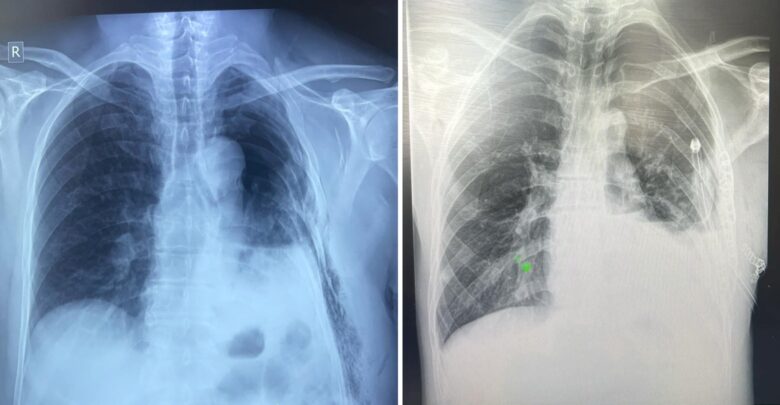

Тухайлбал, Ховд аймгийн Бүсийн оношлогоо эмчилгээний төвийн гэмтлийн эмч Б.Батбулган, мэдээгүйжүүлгийн эмч Б.Батбаатар, мэдээгүйжүүлгийн сувилагч Н.Ганчулуун, мэс заслын сувилагч Ц.Отгонжаргал, туслах сувилагч Д.Ууганцэцэг нартай хамтран авто ослын улмаас цээжний хөндийн хавсарсан хүнд гэмтэлтэй өвчтөнд яаралтай мэс засал эмчилгээ хийжээ.

Мөн Баян-Өлгий аймгийн эрүүл мэндийн төвийн гэмтлийн эмч А.Еркебек, мэс заслын эмч Е.Мурат, мэдээгүйжүүлгийн эмч Б.Ержан, мэдээгүйжүүлгийн сувилагч Ж.Еркетай, мэс заслын сувилагч Лена, асрагч Манар нарын хамт уушгины няцрал, олон хавирганы тогтворгүй хугаралтай, амьсгалын дутагдалд орсон өвчтөнд мэс засал эмчилгээг амжилттай хийсэн аж.